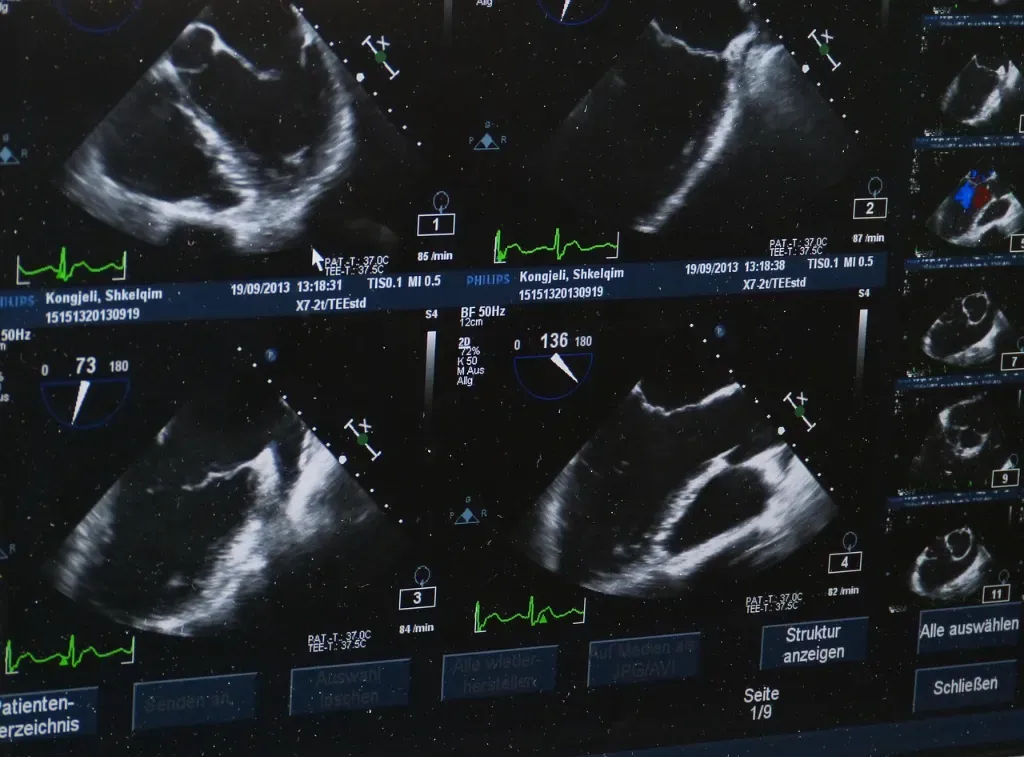

Zastanawiałeś się kiedyś, jak wiele zależy od wyboru odpowiedniego aparatu USG i przede wszystkim, od jego ceny? To pytanie, które pojawia się niemal przy każdej decyzji zakupowej – czy inwestować w najnowszą technologię, czy może wybrać coś bardziej ekonomicznego, ale wciąż skutecznego? Jeśli tak, to koniecznie zagłębmy się w temat, bo aparat usg cena to nie tylko liczba, którą można łatwo porównać w sklepach. To klucz do tego, jak dobrze, szybko i precyzyjnie można diagnozować pacjentów.

Można powiedzieć, że aparaty USG to jak inwestycja w przyszłość gabinetu – od kilku tysięcy do nawet kilkuset tysięcy złotych. To ogromna rozpiętość cenowa, ale co kryje się pod tymi cyframi? Przede wszystkim, za wyższą ceną idą zaawansowane technologie: lepsza rozdzielczość, więcej funkcji obrazowania, możliwość podłączenia do systemów zarządzania pacjentami czy też mobilność i komfort obsługi.

Na rynku dostępne są zarówno modele podstawowe, idealne dla małych praktyk, jak i zaawansowane ultrasonografy, wykorzystywane w dużych placówkach medycznych. Jednak czy to oznacza, że droższy aparat zawsze będzie lepszy? Nie do końca. Podobnie jak w przypadku smartfonów, każdy użytkownik ma swoje preferencje i potrzeby. Warto zatem rozważyć, jakie funkcje będą najczęściej używane i czy inwestycja w droższy model się opłaci.